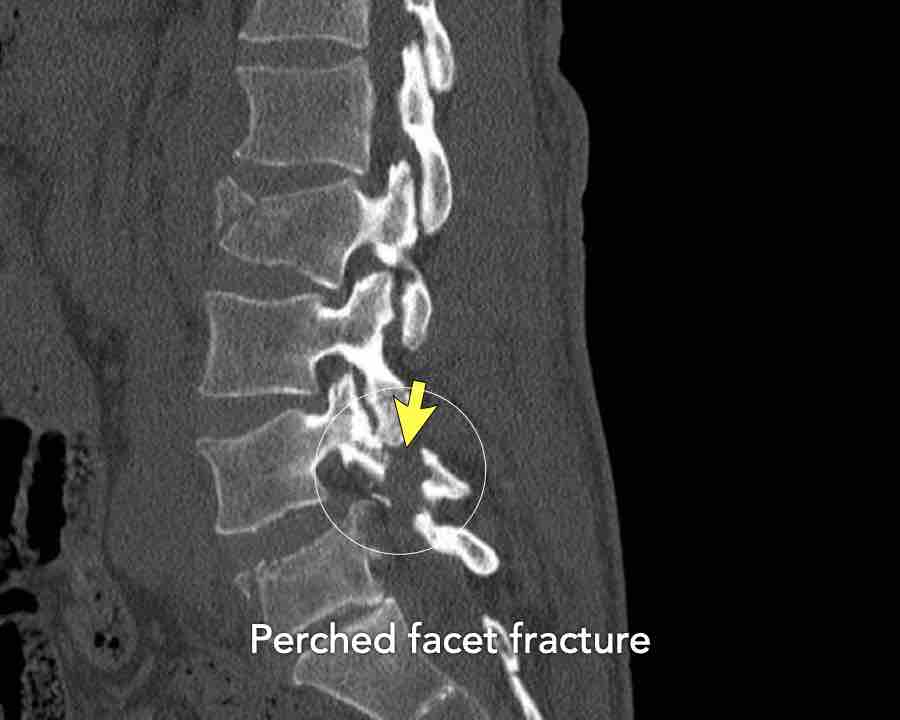

First look at the images.

What are the findings?

What is the highest AO-type of injury?

Findings

- Both facet joints are perched or displaced (black arrows).

The displacement of the vertebrae (white arrow) is not as striking as in previous cases. - There are fractures of the spinous processes on multiple levels.

This is a common feature in C injuries. - Pay attention to the chip fractures on the endplates.

Conclusion

Type C + A1 injury.